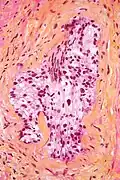

Le ghiandole neoplastiche sono tipicamente più piccole, affollate e rigide delle normali; presentano iperplasia massiva, con perdita delle papille e dello strato basale esterno. Le normali colorazioni evidenziano un nucleo grande, provvisto di nucleolo, contornato da citoplasma chiaro o talora intensamente eosinofilo (con caratteristica colorazione rosa-violacea omogenea).[57] Benché queste isole neoplastiche siano di facile individuazione, la diagnosi istologica potrebbe rendersi difficile per la mancanza di pleomorfismo e di figure mitotiche atipiche, tuttavia l'elevato monomorfismo e la rigidità dell'aspetto degli acini affollati, con cellule e nuclei posti in posizioni monotone all'interno del focolaio di adenocarcinoma, permettono un'agevole distinzione dalle ghiandole normali, tipicamente più variegate nell'aspetto, con profili tortuosi e cellule disposte in modo fisiologicamente disordinato, con citoplasmi chiari secretivi e nuclei piccoli e allungati, affusolati, blu-viola scuri, diversi da quelli rigidamente tondi e nucleolati del carcinoma. Talora però i focolai neoplastici rilevati nei frustoli bioptici ottenuti con ago tranciante sono molto piccoli e con caratteristiche valutabili su un ristretto numero di acini sospetti. Normali colorazioni con ematossilina-eosina che mostrino ghiandole piccole, affollate di cellule con perdita delle papille possono in questi casi essere solo suggestive di carcinoma prostatico; la diagnosi viene avvalorata qualora si presentino una o più di queste caratteristiche:[57]

- Nuclei grandi e amorfi, citoplasma scuro, nucleoli prominenti.

- Assenza di cellule basali nel contesto delle ghiandole basali (ricercate con marcatori immunologici)

- Invasione perineurale (vedi immagine)

Frustolo bioptico, colorazione cromo-ematossilina-floxina. Nella porzione centrale, il frustolo è attraversato perpendicolarmente da un nervo, infiltrato da un piccolo gruppo ghiandolare neoplastico in basso. Questo è un tipico esempio di invasione perineurale.